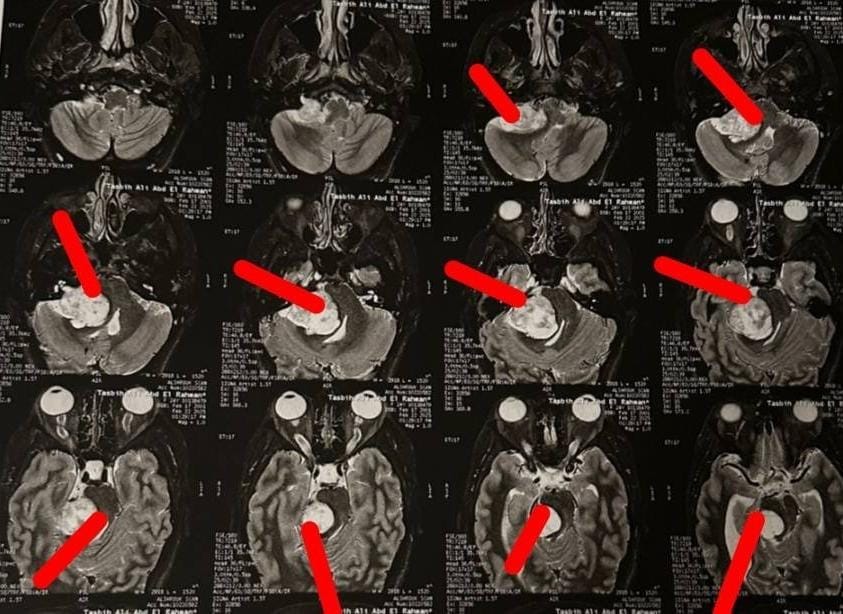

أورام الزاويه المخيخيه

بعد

قبل